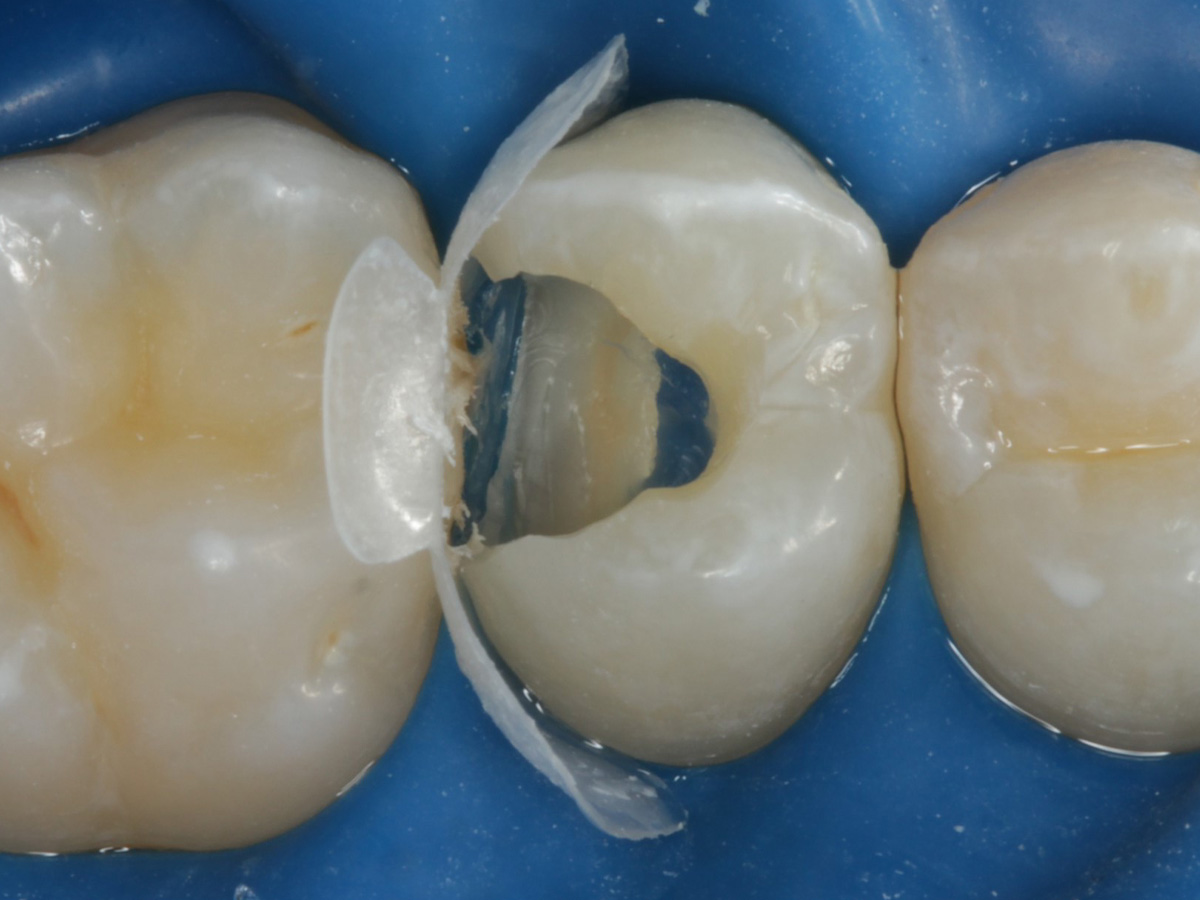

Abbildung 24

Folgesitzung: Trepanation Zahn 25